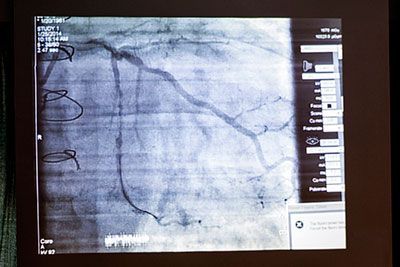

Активное участие в работе курса принимали приглашенные французские коллеги Ив Лувар и Жак Монсегю. На курс приехали 100 специалистов из разных регионов России, заседания вели ведущие отечественные интервенционные кардиологи. Доклады, лекции, разборы клинических случаев сопровождались живой дискуссией, обменом мнениями, спорами. Особый интерес вызвали трансляции из операционных в прямом эфире, которые проводили сотрудники ЦЭЛТ под руководством профессора А.М. Бабунашвили, а также известные российские специалисты из ведущих научных центров страны. Успешно выполнены операции у больных с ишемической болезнью сердца, нарушениями мозгового кровообращения, атеросклерозом артерий нижних конечностей. Продемонстрирован уникальный подход в лечении миомы матки доступом через лучевую артерию.